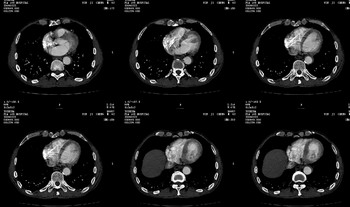

男 62 夜间突然腹痛并向背部放射 ,急诊疑胰腺炎 ,胰淀粉酶正常 ,ct示胰腺未见明显异常,发现降主动脉密度欠均,做主动脉造影示胸腹主动脉半月形低密度充盈缺损,内膜钙化并内移,累及腹腔干致根部明显狭窄,未见明显破裂口。 本人为是不典型夹层,其他人有说是动脉硬化或动脉炎的。请大家发表一下看法。

大动脉炎,左侧房室缺血.

我觉得这个不像主动脉夹层,应该是血栓多点,如果可以重建个mpr也许对诊断更有帮助。